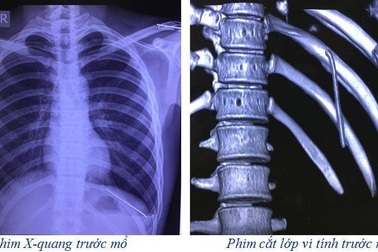

Kỳ lạ chiếc đinh "chui" xuyên qua phổi, tuỷ sống bệnh nhânCác bác sĩ BV Đa khoa Đức Giang vừa thực hiện ca can thiệp đặc biệt, rút chiếc đinh vốn có tác dụng "ghim" xương bệnh nhân sau một cuộc phẫu thuật đã bị tuột khỏi xương, chui vào tuỷ sống.

Kỳ lạ nam thanh niên cảm nhận chiếc đinh di chuyển trong cơ thể"Những ngày đau đớn, tôi phải chiều chiếc đinh lắm. Nó di chuyển đi đến đâu thì tôi phải nằm xoay người theo nó mới có thể chịu nổi được những cơn đau hành hạ", nam bệnh nhân chia sẻ.